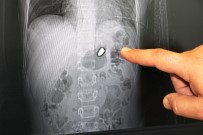

Arda'nın Vücudundan 20 Milimetrelik Serseri Kurşun Çıkarıldı

9 Ekim 2018 Salı

Şanlıurfa'da Bir Çocuğun 'Maganda Kurşunuyla' Yaralanması

8 Ekim 2018 Pazartesi